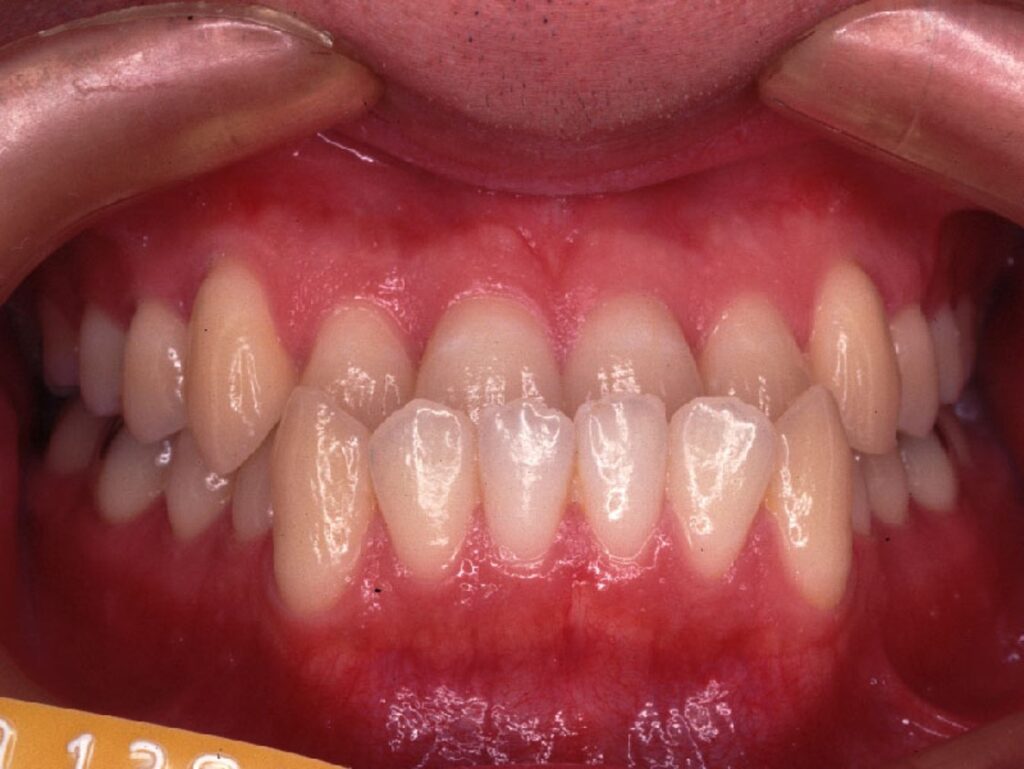

「開咬(かいこう)」といって、前歯が噛めない人がいます。

噛んでもらうと、奥歯だけ噛んで前歯が当たらない人です。

開咬の人は一見すると、歯の並びは綺麗に並んでいるため、自分が歯並びが悪い(噛み合わせが悪い)という事に気づいていません。開咬の人は、麺類などを前歯で噛み切ることができません。しかし今まで指摘されていなければ、そういうものと生活しているので、正しい噛み合わせの人は前歯が食べ物が噛み切れることを説明すると驚かれます。

この「反対咬合」と「開咬」の方に共通していることは、「奥歯しか噛めない」という事です。通常、歯は上下・全体で噛み合って負担を分散するのですが、前歯が噛めない人は奥歯に過重負担が起こります。それにより、奥歯に亀裂やヒビが入り、その隙間から虫歯菌が侵入することが多くあります。これが他の人より虫歯になりやすい原因です。

「叢生」「反対咬合」「開咬」の人の解決方法は「矯正治療」です。歯並び、噛み合わせをよくする歯列矯正をすることで、虫歯リスクを減らすことが可能となります。噛み合わせが良い人は噛み合わせの悪い人に比べて、80歳になった時に歯の残っている本数が多いことがデータで出ています。つまり、噛み合わせが安定していると、歯の治療を受けることが少ないのです。治療していない天然の歯が残っていることは歯の寿命が長いこととも言えます。